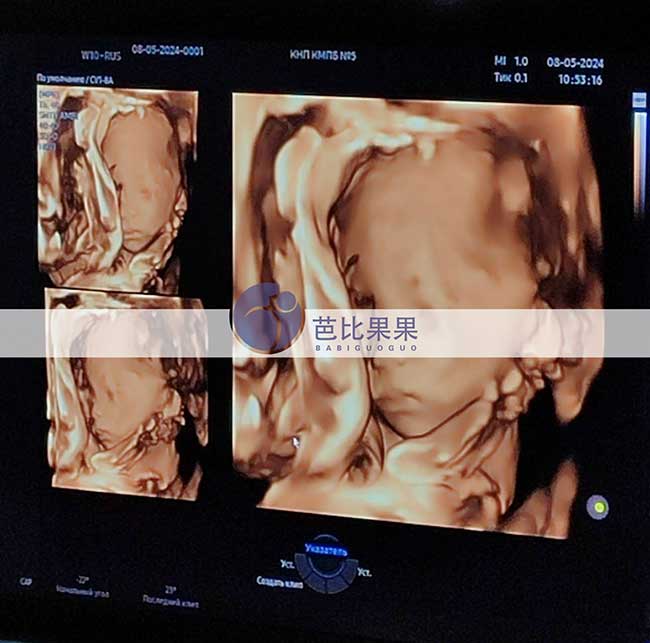

F女士在格鲁吉亚补偿的乌克兰试管妈妈来做四维彩超

F女士在格鲁吉亚补偿的乌克兰试管妈妈来做四维彩超啦,看到了小宝贝可爱的小脸,感谢美丽的试管妈妈。